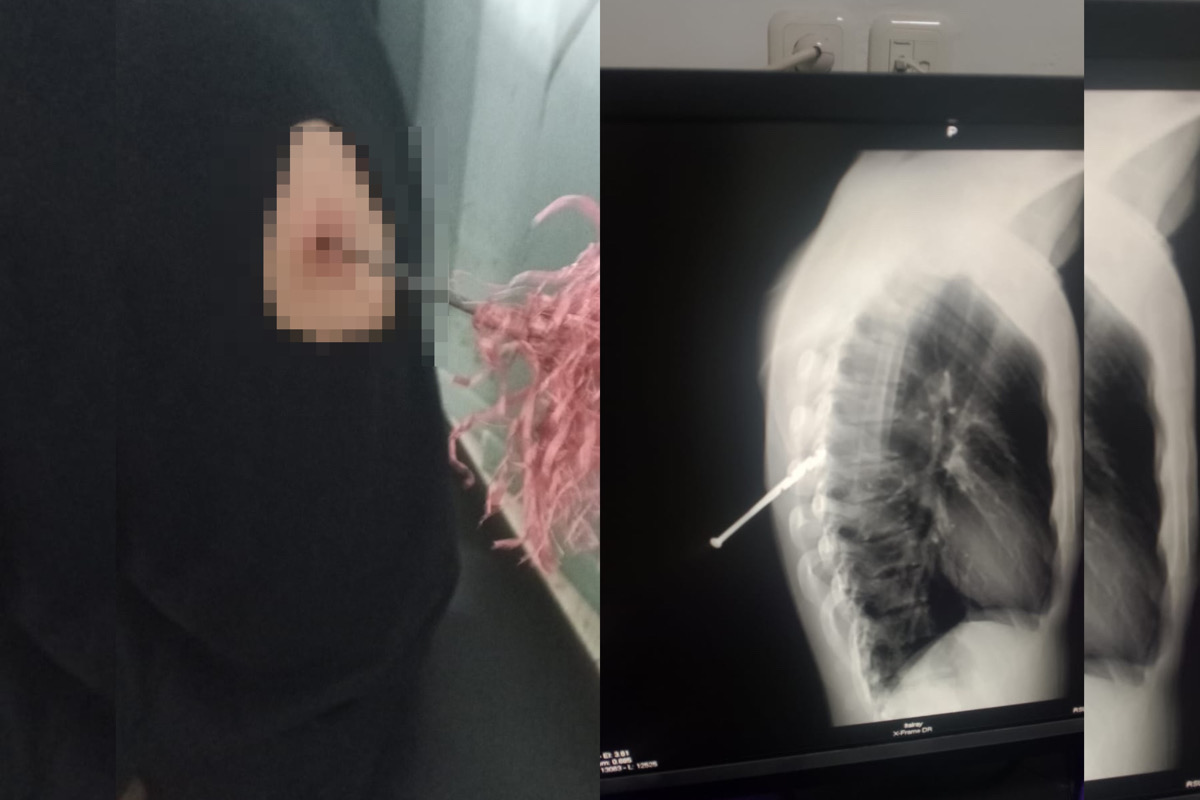

MUNA, SULTRAINFORMASI.ID – Seorang pemuda bernama Muhammad Ikhsan menjadi korban pembusuran saat melintas di wilayah Desa Wapunto, Kecamatan Duruka, Kabupaten Muna, Sulawesi Tenggara (Sultra) Minggu (18/01/2026) dini hari. Peristiwa tersebut terjadi sekira pukul 02.00 WITA.

Tanpa diduga, salah satu orang dari kelompok tersebut tiba-tiba melepaskan mata busur ke arah korban. Anak panah tersebut mengenai punggung sebelah kiri korban, sehingga menyebabkan luka,” katany Jufri.